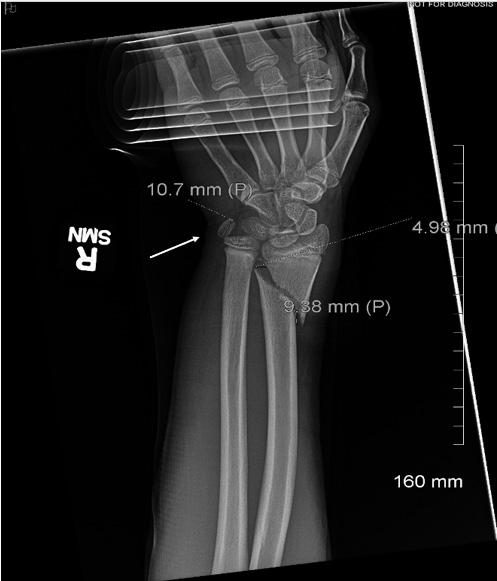

- CAL/AAEM News Service email updates - Discounted AAEM pre-conference fees

- And more!

CAL/AAEM NEWS SERVICE

- Healthcare industry news

- Public policy - Government issues - Legal cases and court decisions